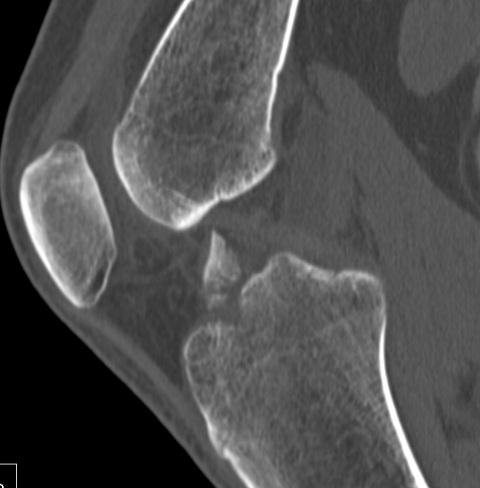

CT

Can help classify and thus guide treatment

Type II Type III

Type IV